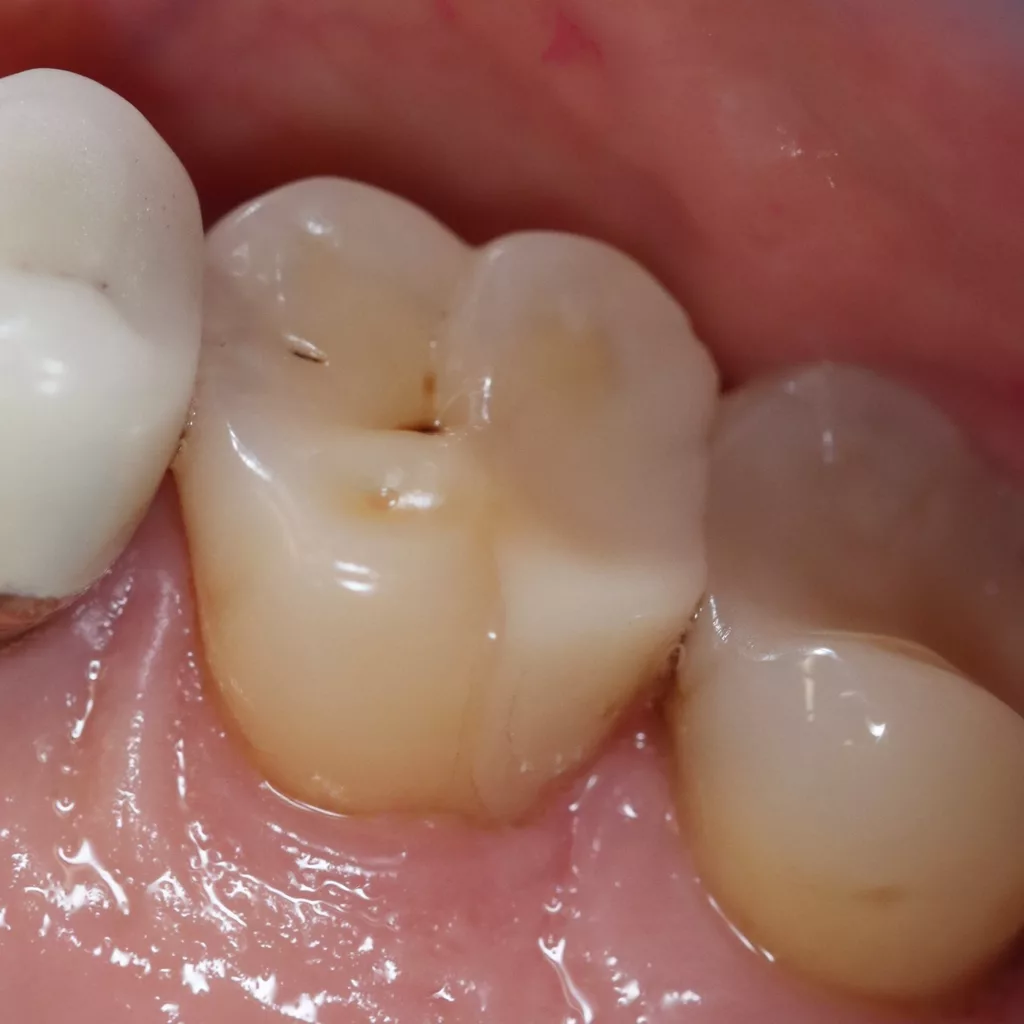

Wird eine profunde kariöse Läsion behandelt, empfiehlt sich folgendes Vorgehen [5]: Zunächst sollte in einem ersten Schritt ein Kofferdam appliziert werden, um eine möglichst keimfreie Arbeitsweise zu gewährleisten. Nach Präparation einer Zugangskavität, wenn dies notwendig ist, erfolgt die Kariesexkavation mittels Rosenbohrern oder Handexkavatoren. Wird in pulpanahen Arealen eine Eröffnung der Pulpa erwartet, sollte das Instrument gewechselt und ein sauberer Rosenbohrer genutzt werden. Tritt nach vollständiger Kariesexkavation keine Eröffnung der Pulpa ein, ist aber von einer dünnen Restdentindicke von etwa 300 µm auszugehen, oftmals erkenntlich durch eine zartrosa hindurchschimmernde Pulpa, sollte nach Kavitätentoilette mittels Natriumhypochlorit (NaOCl) 3% eine indirekte Überkappung mit einem hydraulischen Kalziumsilikatzement erfolgen [5]. NaOCl dient dazu, Bakterien und Toxine zu neutralisieren und das Dentin zu desinfizieren. Die Unterfüllung aus Kalziumsilikatzement soll auch desinfizierend wirken, das Pulpagewebe zur Heilung anregen und vor möglicherweise durch das Dentin penetrierenden Monomeren aus dem Dentinadhäsivsystem schützen [5], da diese die regelrechte Funktion der Odontoblasten beeinträchtigen können [9,40]. Im Anschluss muss eine direkte, dentinadhäsive Restauration zur Versorgung der Kavität platziert werden [5]. Die Abbildungen 1 bis 14 illustrieren das Vorgehen bei der Behandlung einer profunden kariösen Läsion mit indirekter Überkappung der Pulpa.